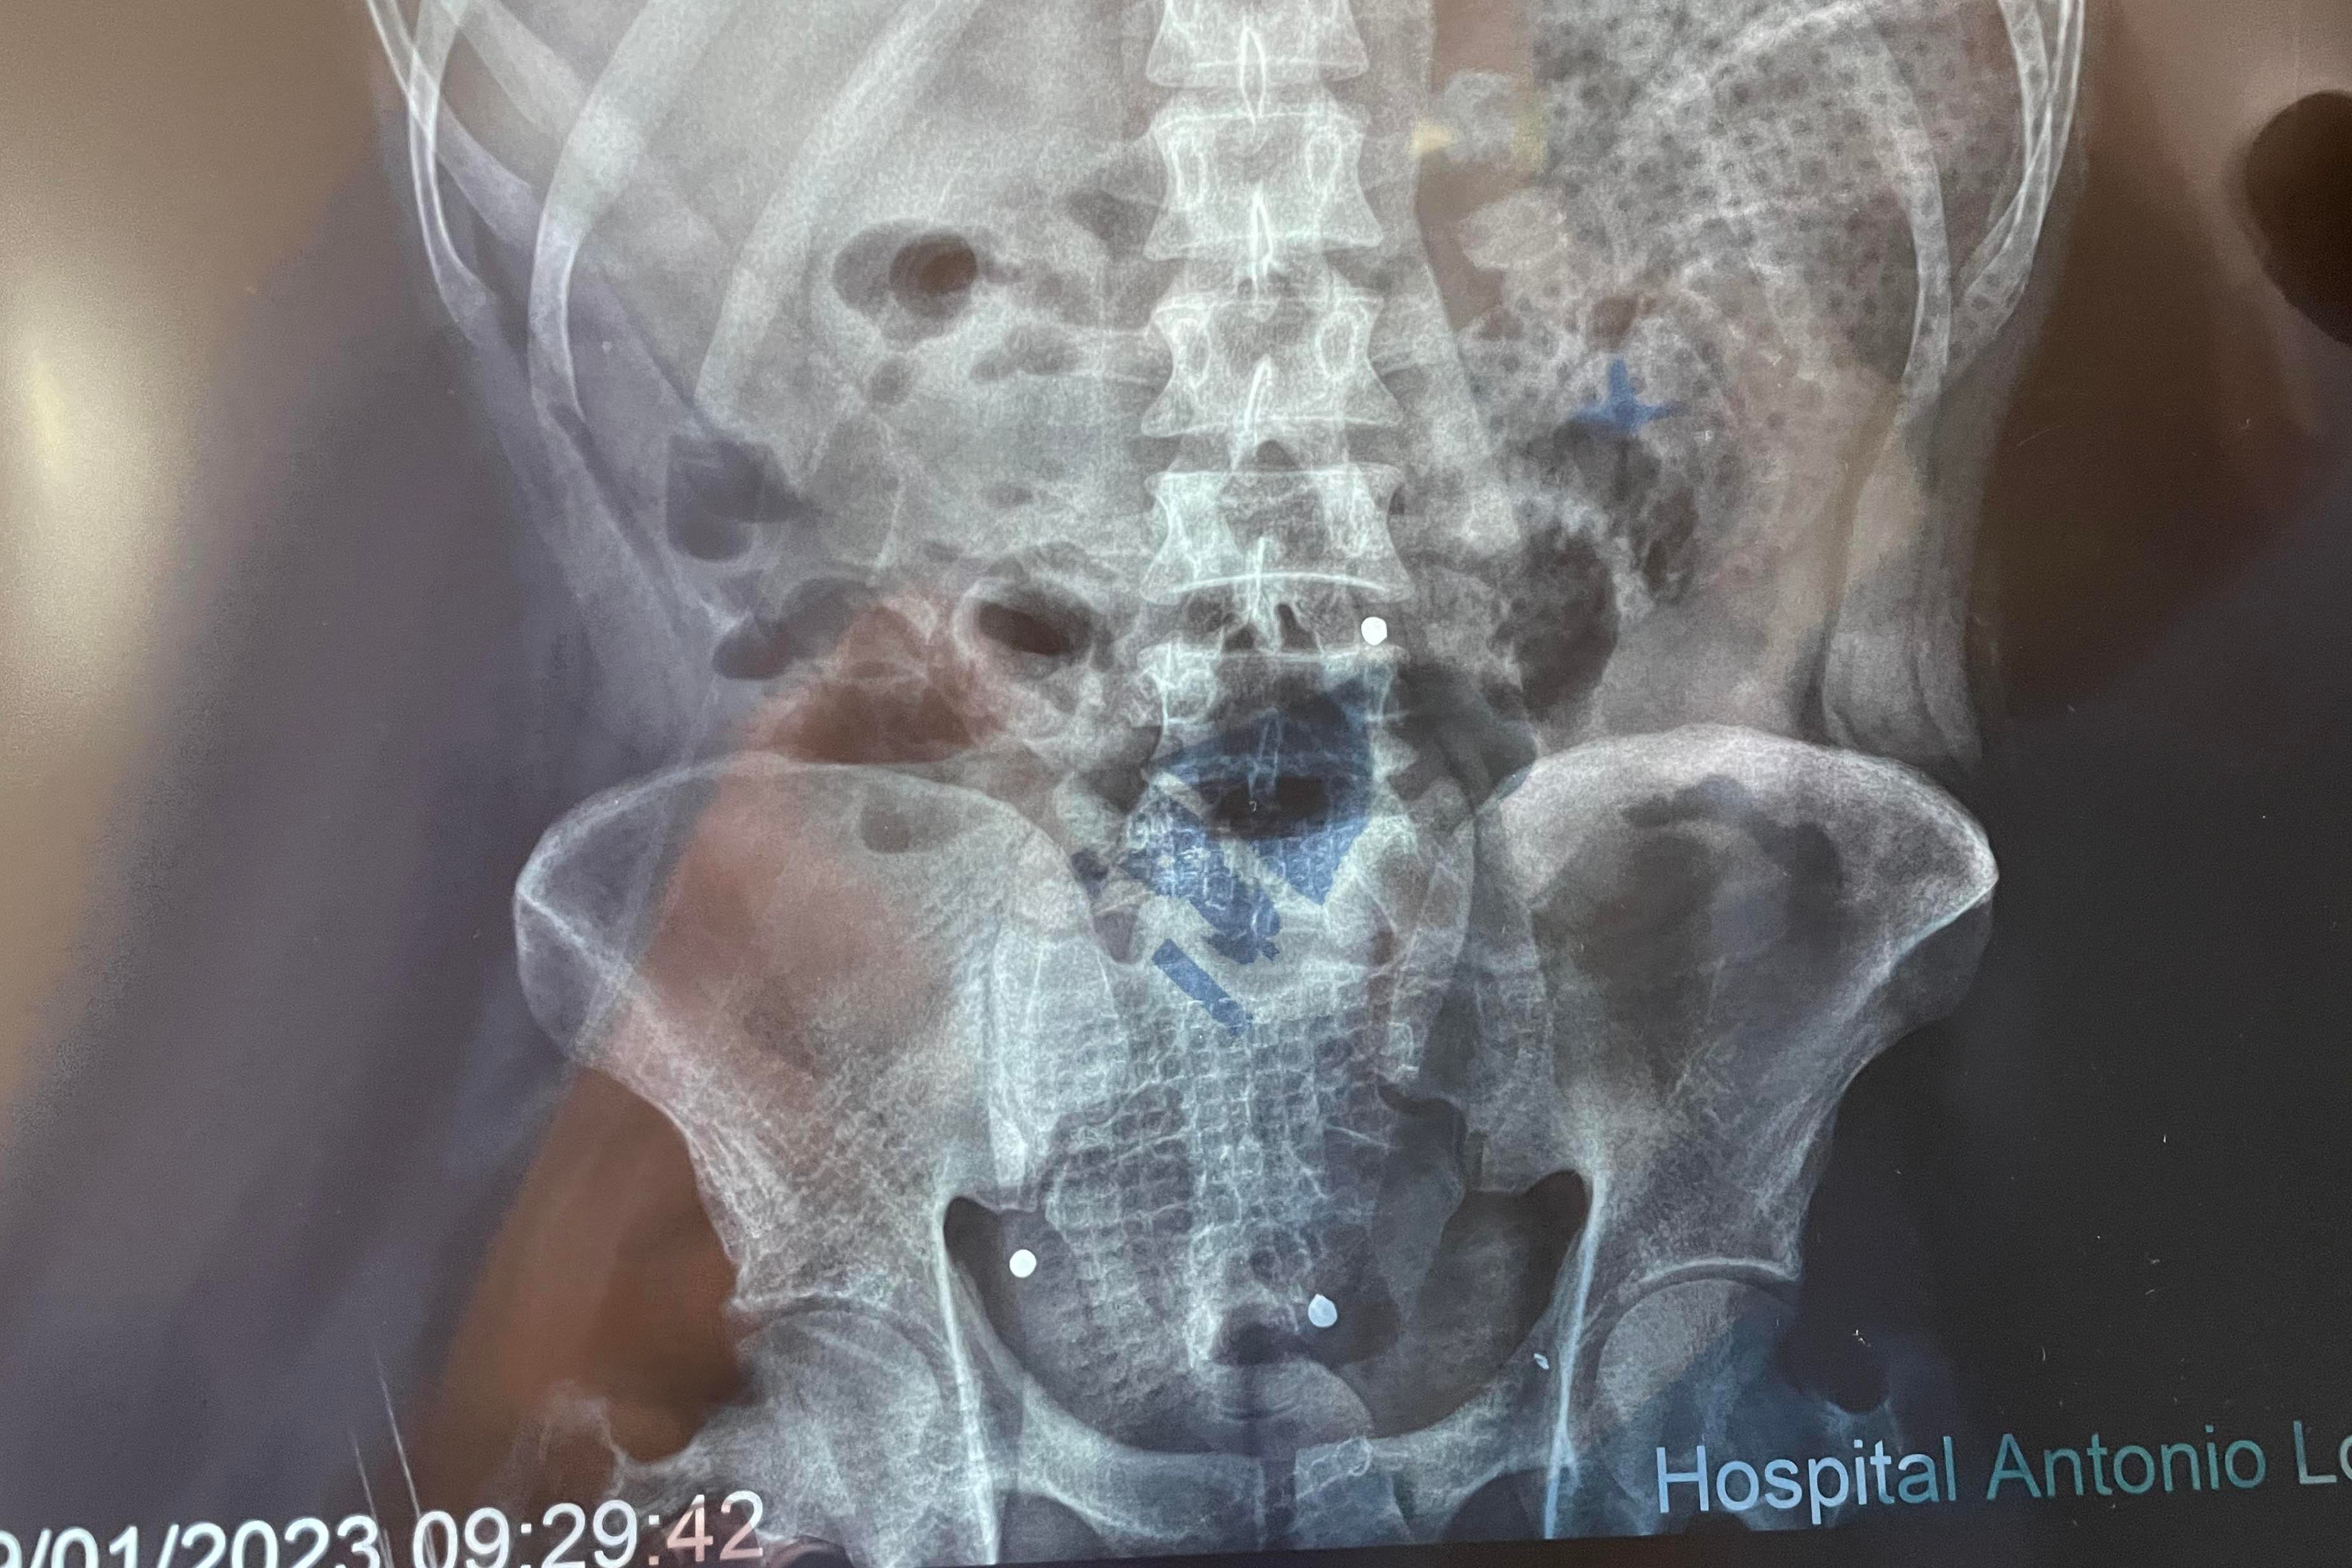

An X-ray shows three of the five pellets that hit Quispe.